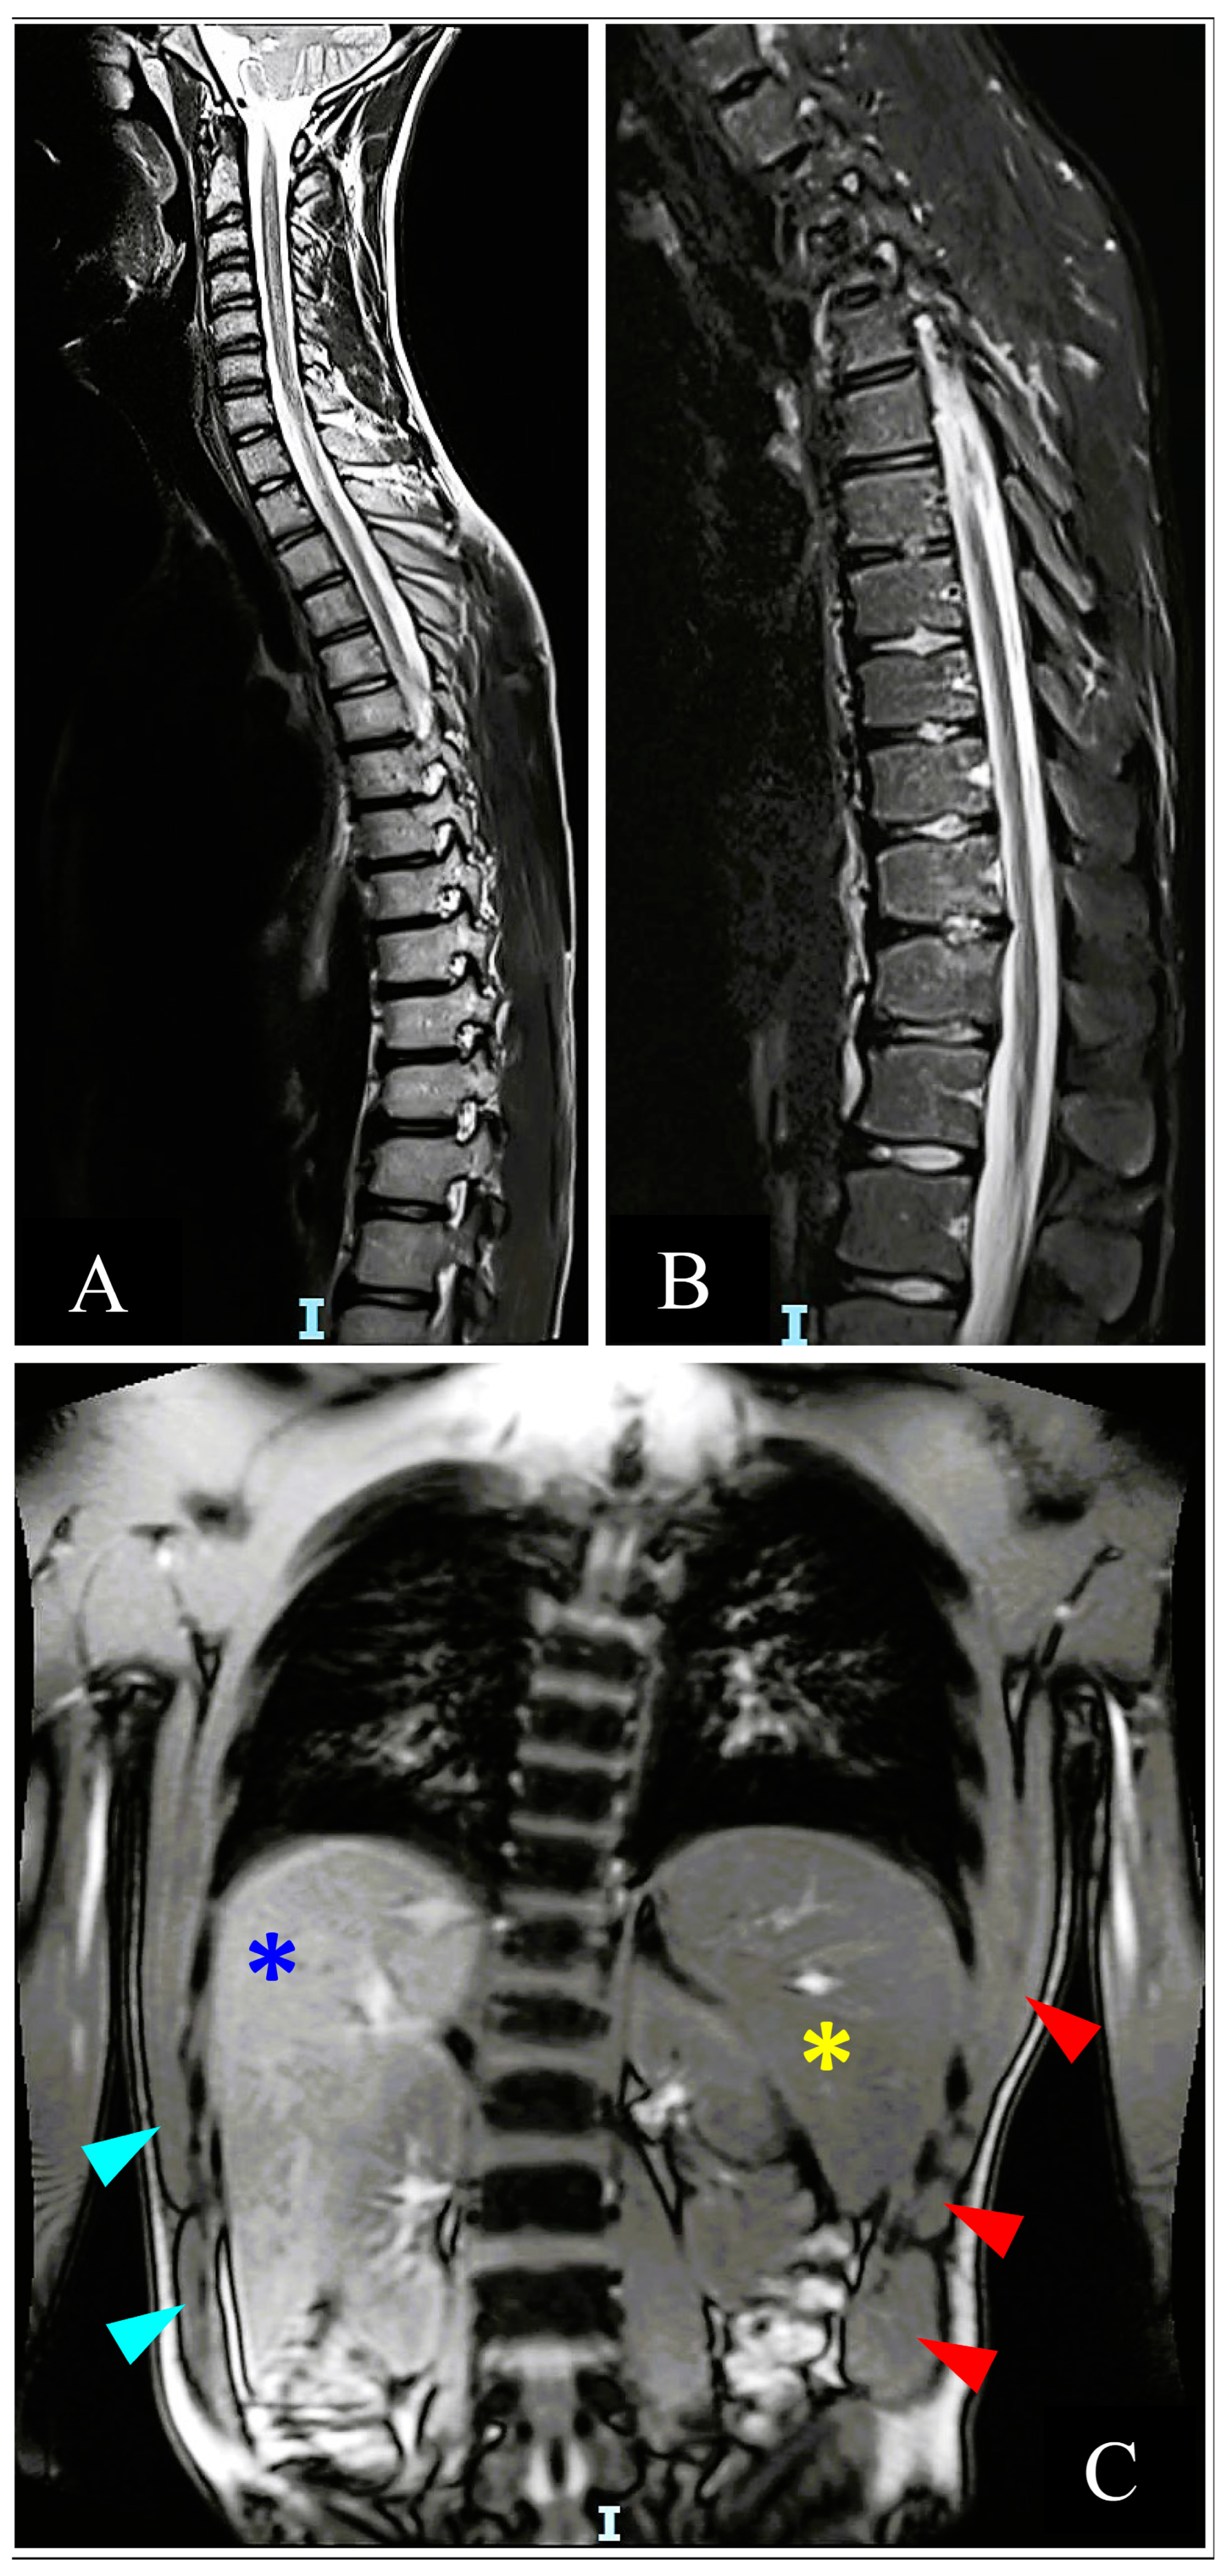

3.3.2. Imaging